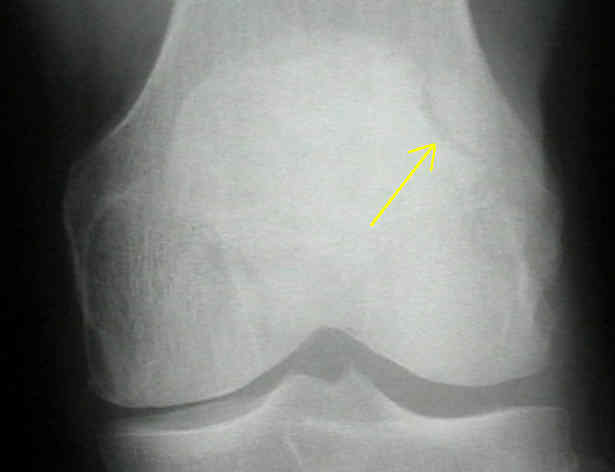

20. 이분 슬개골이란 무엇인가?

이분 슬개골이란 또 하나의 정상적인 해부학적 이형으로, 슬개골 골절로 잘못 판별해서는 안 된다. 이차적 골화 중심으로 슬개골 사분면의 상외측에서 보인다. 대개 대칭적이며, 매끄럽고 경화성의 외피 경계를 가진다.

△ Bipartite patella (이미지 출처 : http://www.wheelessonline.com/ortho/bipartite_patella)

21. Segond 골절이란 무엇이며, 임상적으로 암시하는 바는 무엇인가?

Segond 골절은 외측인대 부착부의 근위 외측 경골의 견열 골절을 말한다. 골절 파편은 매우 작을 수 있다. 방사선 사진 상으로 보기에 매우 힘듦에도 불구하고, 흔하게 전방십자인대 파열과 반월상 연골판 손상이 동반된다.

△ Segond fracture (이미지 출처 : http://www.medicinadurgenza.org/)

△ D는 Segond 골절에 해당. 근위 외측 경골의 견열 골절(화살표)에 해당한다.